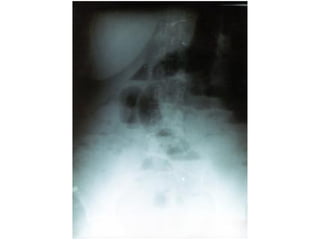

• RADIOLOGIA

• Teleradiografia de torax PA y lateral  Aire libre

subdiafragmatico

• Placas simples de abdomen

• De cúbito  Patrones gaseoso

• De pie o de cúbito lateral  Niveles hidroareos

• Estudio baritado con control de fluoroscopio

• TAC

Obstrucción intestinal